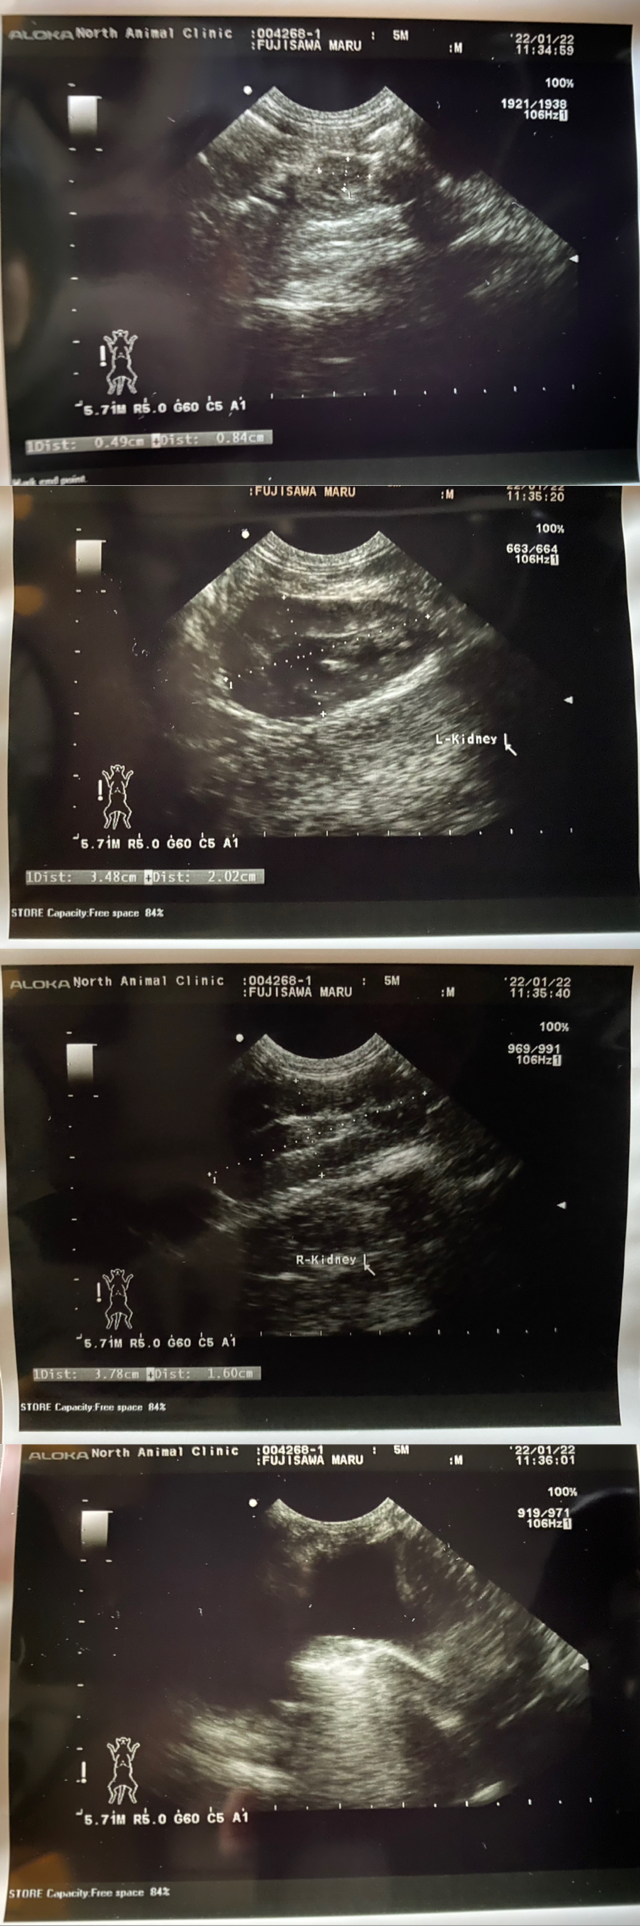

不安になり、12月29日に他動物病院へ連れて行ったところ、胸水が溜まっていて呼吸がとても困難な状態だと伝えられました。

更に色々と検査をしていただき胸水も抜いてもらうことになりましたが、小さな身体ですし痛くて暴れてしまうのもあり、全ては抜けませんでした。

貧血を起こしており、肉芽腫も発見されたため、判断の余地なく、すぐに入院をすることになりました。

FIPは「ウェットタイプ」と「ドライタイプ」、もしくは「混合タイプ」に分類されます。 円(マル)の場合は、貧血.微熱.肉芽腫.胸水があるので、混合タイプのFIPだと診断されています。

以下に病院にて診察・検査・治療薬処方の際に出ている明細書を載せさせていただきます。

(現在:治療.投薬中)

投薬初期(22.01.08~22.02.04)で

3,300円(100mg)+6,600円(200mg)=9,900円

体重増加の為、現在(22.02.05~)一日あたり

13,200円(200mg×2)